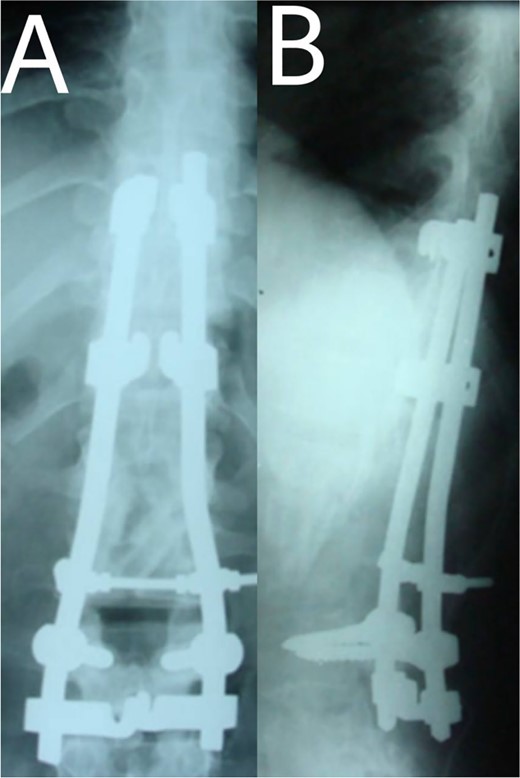

A 24-year-old farmer female was admitted to the Department of Neurosurgery with low back pain, no fever, cough, motor deficit, or any symptoms. Medical, surgical, family histories and physical examinations were unremarkable. The laboratory findings showed a white cell count of 9.8 × 103/μL, C-reactive protein concentrations of 20, erythrocyte sedimentation rate of 50 mm/1 h, 90 mm/2 h and tuberculin skin test was positive. X-ray films showed the collapse of the L1, L2 vertebrae, and L1–2 intervertebral space (Fig. 1). An abscess was observed at the L1–L2 vertebral level in lumbar magnetic resonance imaging (MRI) (Fig. 2). Chest X-rays and Sputum smear were negative. The patient was treated with anti-TB treatment (Isoniazid, Rifampicin, Ethambutol, Pyrazinamide) due to spinal TB findings on MRI (Fig. 3). After 40 days, the patient was diagnosed with grade 1/5 lower limb weakness, and bladder and bowel dysfunction, with no impairment in sensation, which predicts spinal infection. MRI confirmed these abnormalities and showed typical findings such as vertebral endplate destruction, bone marrow and disk signal abnormalities, and paravertebral or epidural abscesses (Fig. 3). Due to clinical manifestations and MRI spinal TB findings (Fig. 3), the patient underwent surgical debridement, interbody fusion and internal fixation with fibular autografting and supplemental posterior spinal stabilisation using a posterior-only approach. On post-operative follow-up, the treatment continued for 9 months, in addition to physical therapy for lower limb weakness. In the end, the patient returned to full motion with grade 5/5 in the lower limb, normal sensation, and no bladder or bowel incontinence. No recurrence was observed in the grafting area. Radiologically 2, 6 and 12 months, 14 years’ post-operation, the patient had achieved full bony graft spinal fusion (Figs 4–6).

(A, B) Post-operation, anteroposterior and lateral view showing fibular autograft implantation followed by supplemental posterior instrumentation.